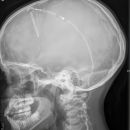

Schädel a.-p.

Fremdkörper-Lokalisation vor MRT, Shuntkontrolle

Symmetrische Abbildung beider Schädelhälften, Nasenscheidewand streng in der Mitte. Die Felsenbeine stellen sich im unteren bis mittleren Drittel der Orbita da. Felsbeinspitzen projizieren sich in die Mitte der Orbita oder eher etwas oberhalb davon.